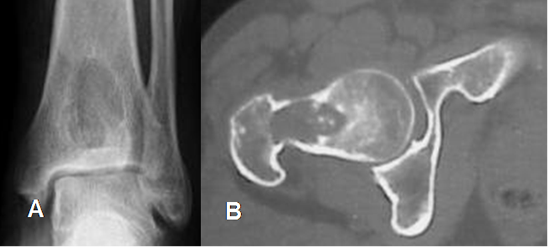

Fig 21. Lesión central.

A: Rx AP. Lesión central en la tibia distal, por quiste simple.

B: TAC axial. Lesión central en el cuello femoral, por condroblastoma.